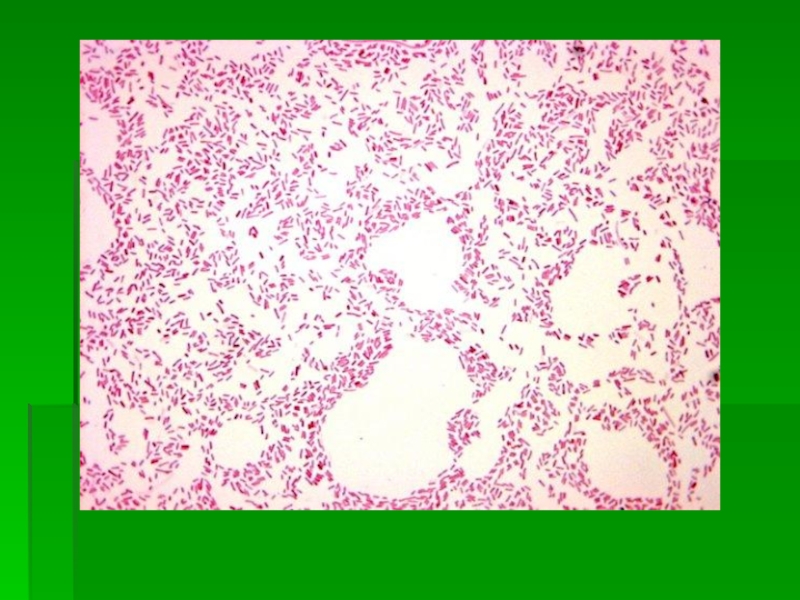

Слайд 6Морфология

Эшерихии мелкие Гр- прямые палочки размерами 1-1,5 х 2-5 мкм.

Могут иметь

капсулу или микрокапсулу

В основном подвижны, но имеются неподвижные штаммы.

В мазках располагаются одиночно или парами